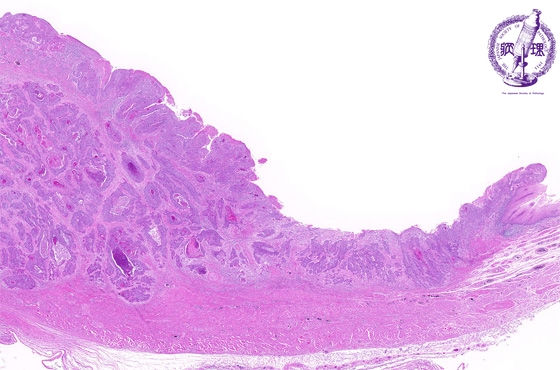

- ★(3)Esophageal carcinoma (squamous cell carcinoma)

Microscopic view (H&E stain, low power): There is squamous cell carcinoma invading into the muscularis propria (arrow: boundary between normal mucosa and carcinoma, dotted line: invasion into the muscularis propria).